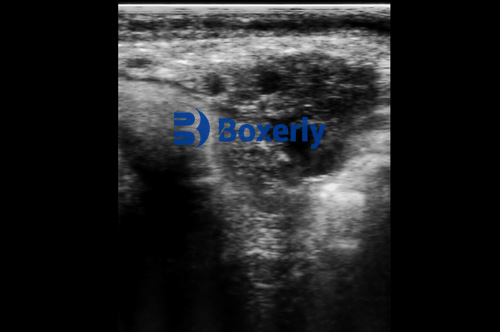

In traditional practices, pregnancy detection was done using manual rectal palpation—a technique that, while effective in skilled hands, lacks the clarity and specificity of modern imaging. Ultrasound has revolutionized this process by providing real-time, high-resolution imaging of the uterus and ovaries. With a transrectal probe, veterinarians can accurately determine whether a cow is pregnant as early as 25 to 30 days post-breeding.

This is where ultrasound proves invaluable. With a linear array transrectal probe, veterinarians can examine the structural integrity and physiological state of the uterus and ovaries. For example:

Endometritis appears as thickened uterine walls with fluid echoes.

Pyometra shows echogenic pus within the uterus.

Ovarian cysts and inactive ovaries can be visualized based on their size, shape, and internal consistency.